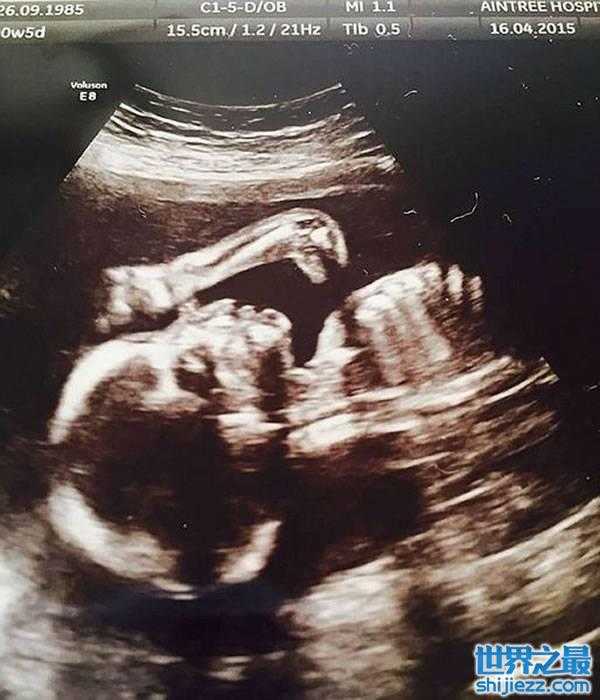

据悉,琳恩是在第20周孕期时去医院做的超声波常规检查,之后她将超声波检查照片拿给朋友们看,在朋友的提醒下琳恩才发觉这张照片中胎儿的轮廓很像是恐龙的样子。琳恩觉得朋友所言极是,之后又专程去电影院看了恐龙电影。据悉,琳恩本身就是一个恐龙迷。

这张引人注目的B超图像酷似生活在侏罗纪晚期的长颈、长头的雷龙。雷龙是一种巨型恐龙,大约生活在1.5亿年前的北美。它们是陆地上存在过的最大型生物之一,臀部约4.5米高,长约23米,体重至少有23吨。琳恩和丈夫将这张超音波扫描照片发布在网上后,立即引发轰动。